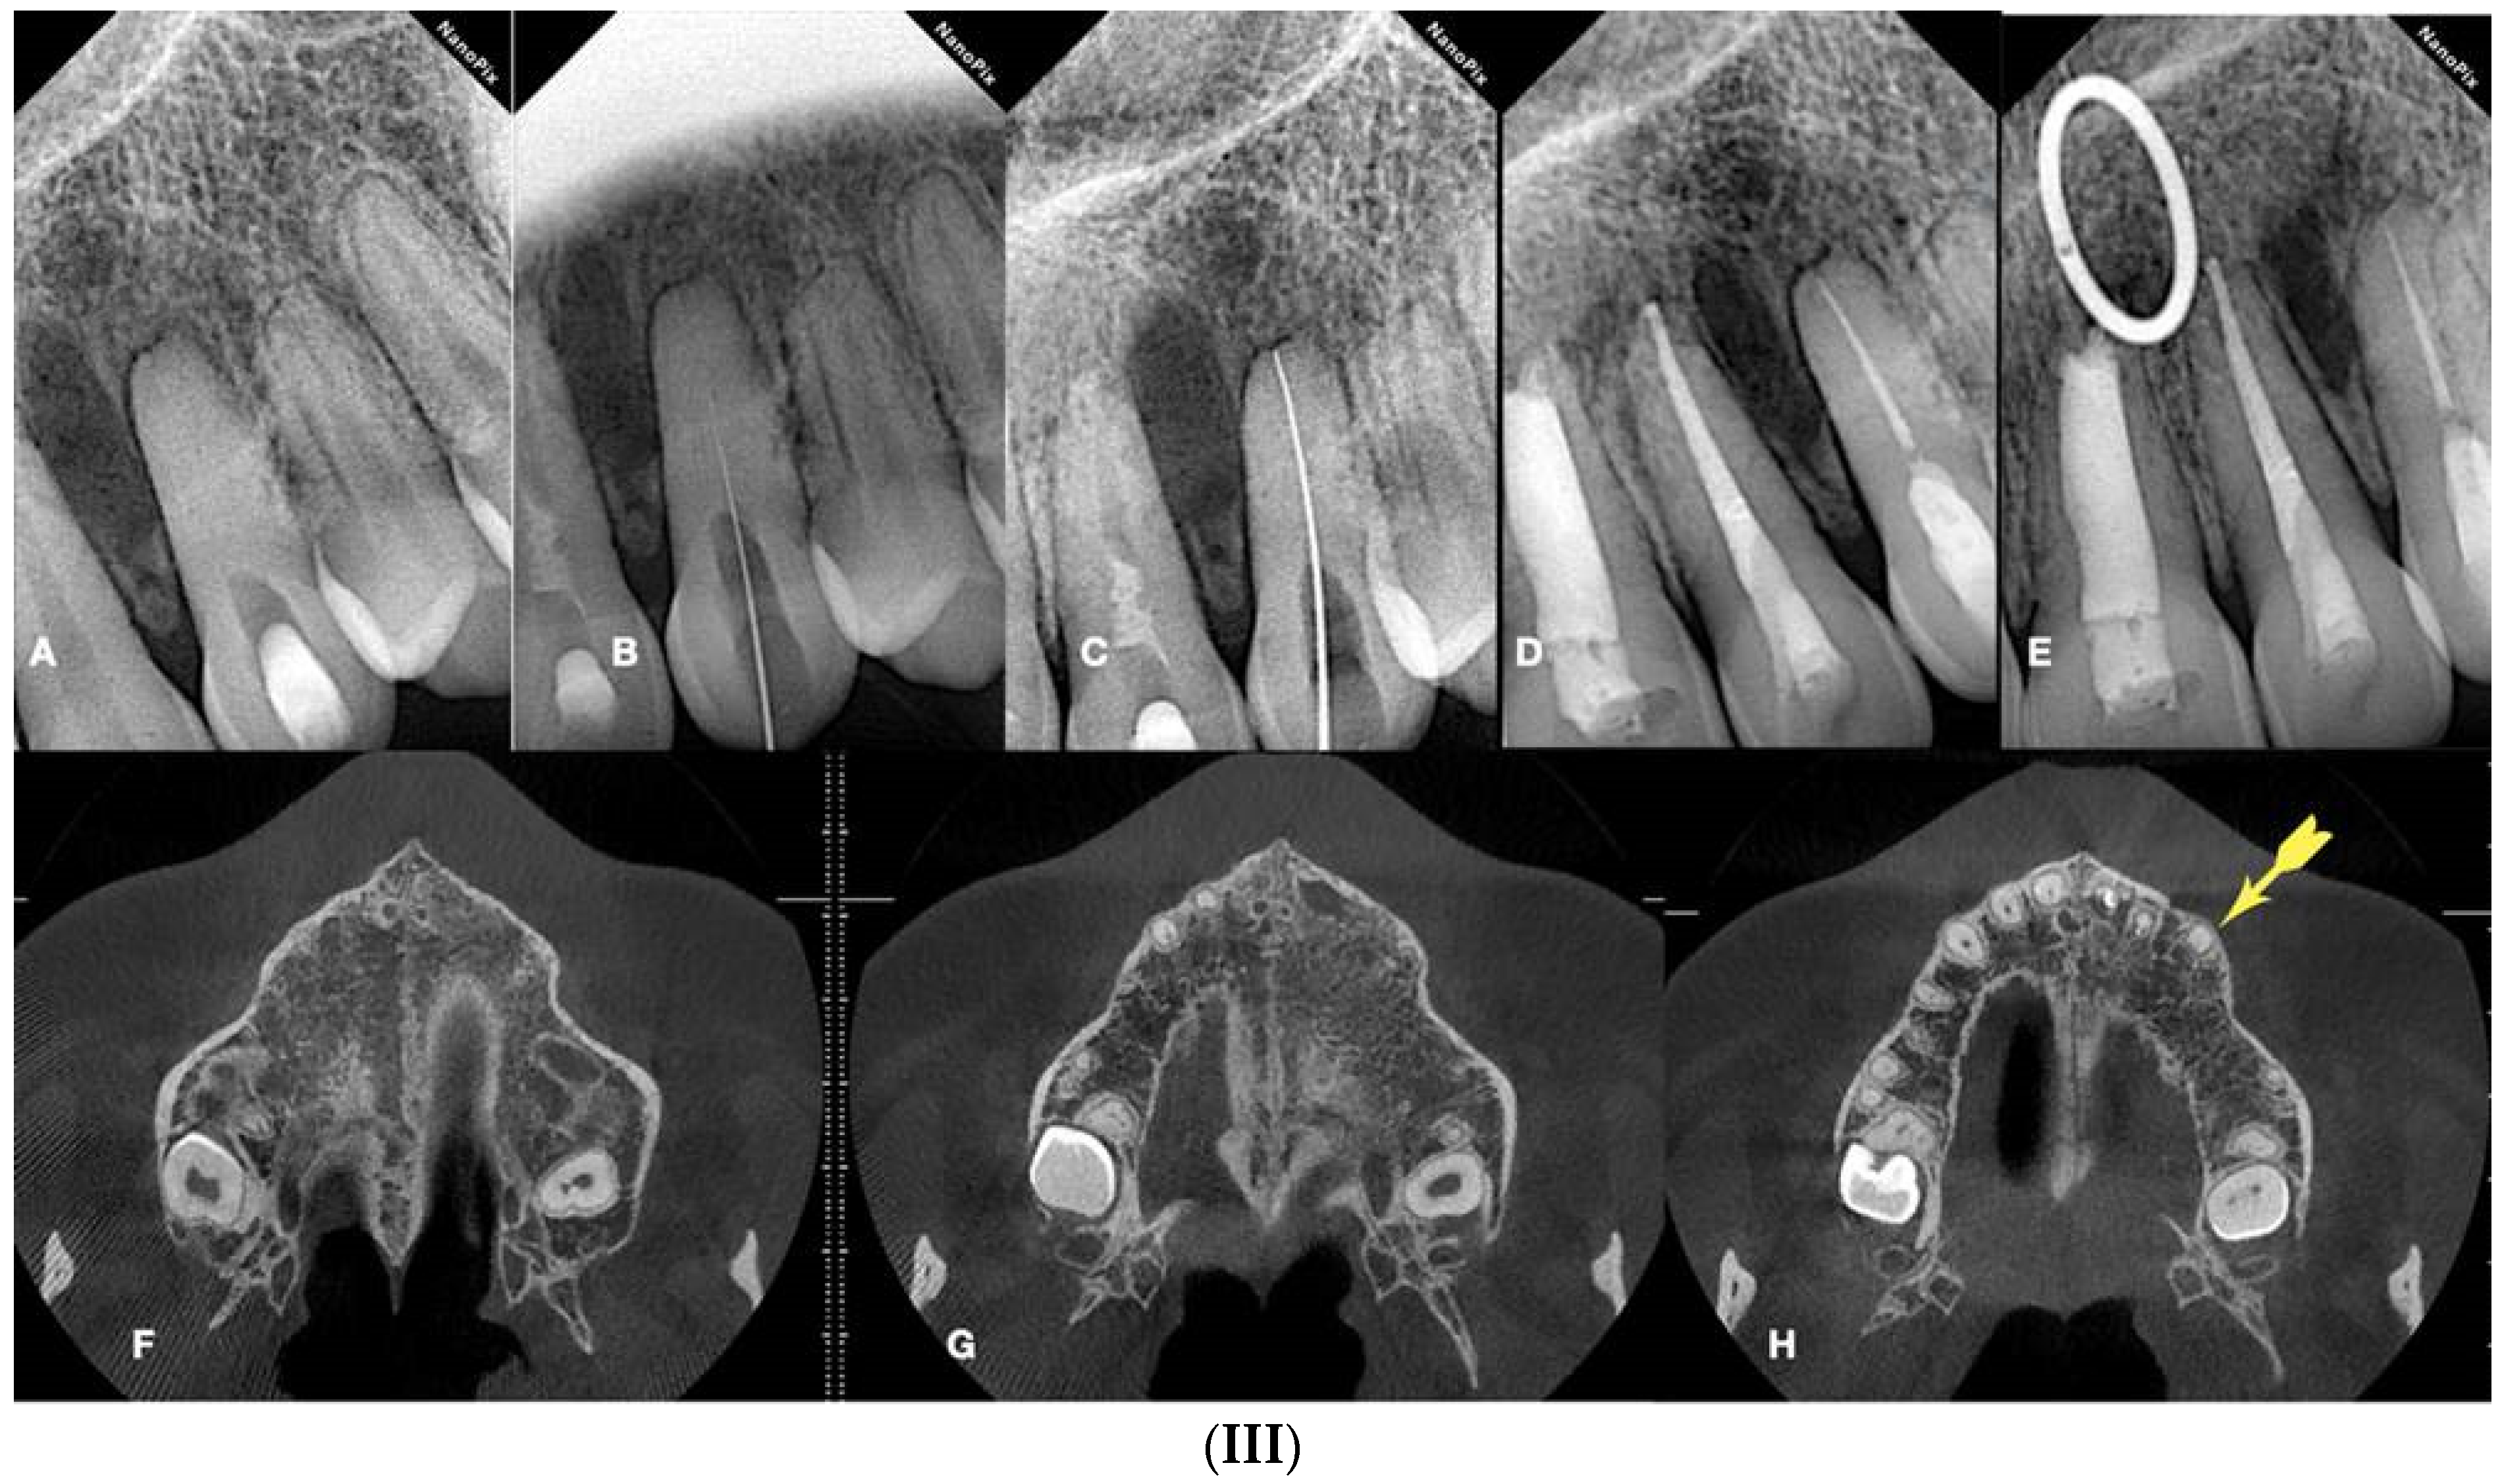

Figure 12.

Calcified maxillary molar negotiation (A). Preoperative radiograph of the maxillary molar with no detectable canals (B). A clinical view of the access cavity reveals a completely calcified chamber (C). Clinical view of the ultrasonic troughing of the pulp floor. Notice that the pulp floor color is grey (D). Clinical view of the axial wall floor junction developmental line (yellow arrow). The canal entrances in a maxillary molar always originate from this line (E–G). Clinical image of the shaped canals. Notice that the location of the canals in a calcified maxillary molar is always lying along the wall–floor junction developmental lines (H). Postoperative radiograph of the calcified maxillary molar treatment (clinical images and radiographs courtesy of Dr. Chaniotis Antonis).

Figure 13.

Calcified mandibular molar negotiation (A). Preoperative radiograph of a calcified mandibular molar with no visible canals (B). Clinical view of the calcified chamber (C). Clinical view of the calcified tissue blocking the access to the mesial canal system. Notice the white color of the calcification. The axial walls are yellow, and the pulp floor is always grey (D). Clinical view of the pulp floor developmental lines after the removal of the white calcified tissue. Chasing the dark grey developmental lines to their termini will reveal the calcified canal entrances (E). Clinical view of the canals shaped (F). Postoperative radiograph of the calcified mandibular molar canal treatment (clinical images and radiographs courtesy of Dr. Chaniotis Antonis). Black arrow: calcified structure covering the canal orifices and the developmental pulp chamber lines, red arrows indicate the canal orifices after the removal of the white calcified structure (black arrow).

Figure 14.

Calcified maxillary premolar negotiation (A). Preoperative radiograph of a calcified maxillary premolar associated with apical periodontitis (B). Clinical view of the palatal calcified canal orifice (red arrow) (C). Clinical view of the buccal calcified canal orifice after chasing the pulp floor developmental line to its far end (red arrow) (D). Clinical view of the EDM file buckling resistance activation test negotiation (E,F). Clinical and radiographic images of the calcified canal negotiation, (G) postoperative radiograph of the calcified maxillary premolar treatment (clinical images and radiographs are courtesy of Dr. Chaniotis Antonis).